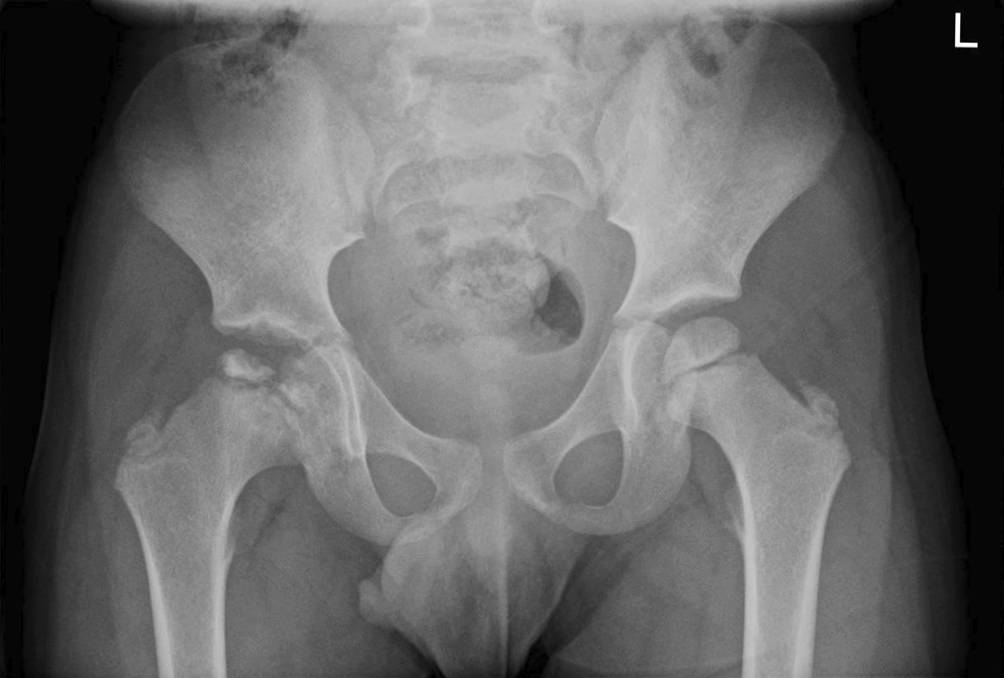

Ein fünfjähriger Junge wird in der Ambulanz der Kinderklinik vorgestellt, weil er bereits seit einigen Monaten sein rechtes Bein beim Gehen ungewöhnlich bewege. Das auffällige Gangbild sei allerdings nicht ständig zu beobachten. Eine Rötung oder Schwellung im Hüftbereich wurde bislang nicht bemerkt. Die Nachfragen zu Infektion oder Trauma werden verneint. Eine Schmerzmedikation sei zu keiner Zeit appliziert worden. Die gestern ambulant durchgeführte Sonografie des rechten Femurs habe allerdings ungewöhnliche Auffälligkeiten ergeben. Daraufhin wird umgehend ein Röntgenbild des Beckens in unserer Klinik angefertigt (Abb. 1).

Abb. 1

Röntgenbild des Beckens, – aufgenommen in einer Ebene – anterior-posterior im Liegen. © Gemeinschaftsklinikum Mittelrhein